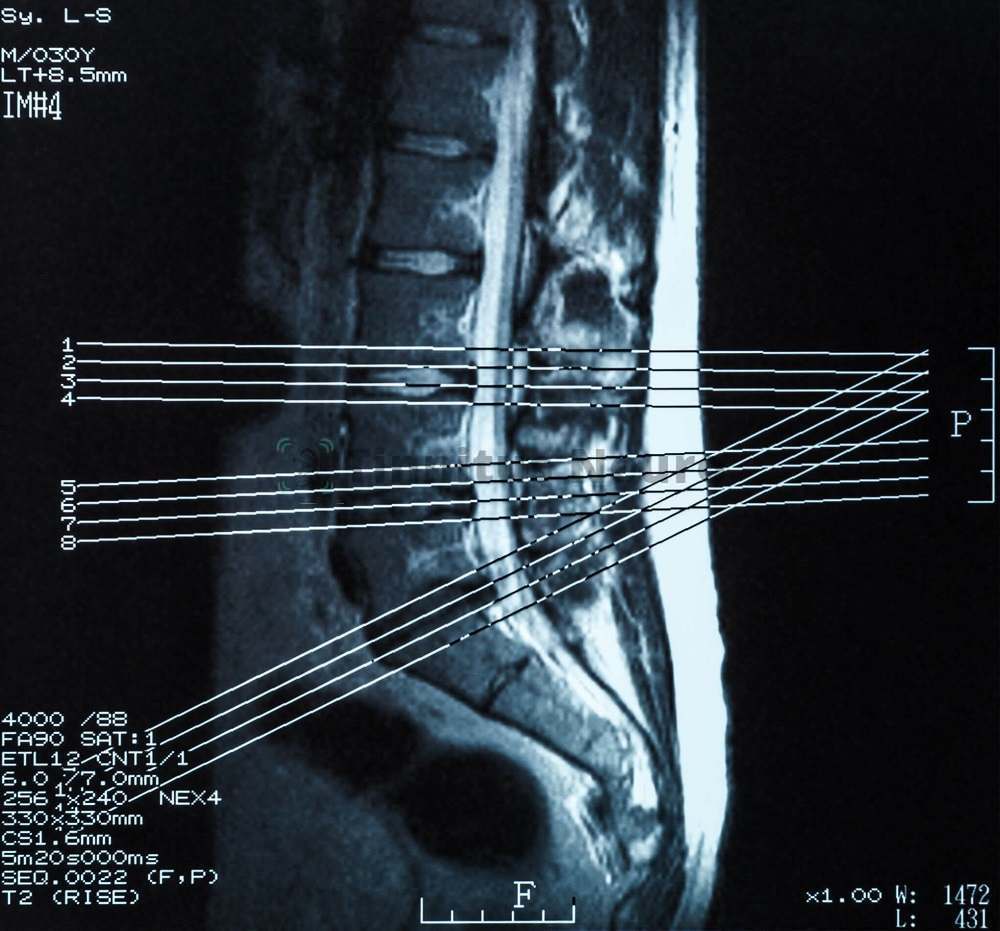

Современный томограф работает за счет улавливания магнитного резонанса, возникающего в человеческих тканях – благодаря этому создается трехмерная картинка во всех имеющихся плоскостях

- На экране томографа появляется трехмерное изображение пояснично-крестцового отдела.